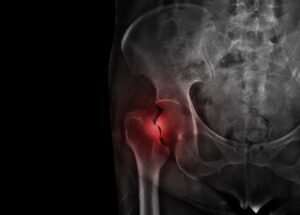

Düşme veya travma sonucu uyluk kemiğinin üst kısmında meydana gelen ciddi bir yaralanmadır. Kalça kırığı yaşlı bireylerde osteoporoz nedeniyle daha sık görülür. Belirtileri arasında şiddetli kalça ağrısı, hareket kısıtlılığı ve bacağın dışa dönmesi yer alır. Tedavi, cerrahi müdahale ve sonrasında fizik tedavi ve rehabilitasyon süreçlerini içerir. Kalça kırıkları, hızlı tıbbi müdahale gerektiren ciddi yaralanmalardır.

Kalça Kırığı Nedir?Kalça bölgesinde yoğun ağrı en yaygın belirtidir. Ağrı genellikle kasık bölgesinde hissedilir ve bacağın hareket ettirilmesiyle artar. Etkilenen bacakta hareket kısıtlılığı veya tamamen hareket kaybı yaşanabilir. Kişi yürümekte veya ayağa kalkmakta zorlanır. Kalça ve çevresinde şişlik, morarma ve hassasiyet görülebilir. Etkilenen bacak, diğer bacakla karşılaştırıldığında daha kısa görünebilir.

Kırık olan bacakta ayak dışa doğru dönmüş olabilir. Bu, kalça kırığı yaşandığının tipik bir işaretidir. Kişi, yaralı bacağını koruma amacıyla farklı bir duruş sergileyebilir. Belirtilerin fark edilmesi durumunda, hemen tıbbi yardım alınmalıdır. Tedavi genellikle cerrahi müdahale gerektirir. Sonrasında fizik tedavi ve rehabilitasyon ile iyileşme süreci desteklenir.